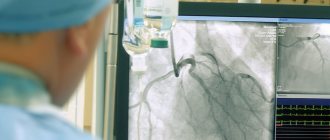

Коронарография проводится под местной анестезией (обезболивается место введения катетера в области бедренной складки). Суть метода заключается в том, что через бедренную артерию, доступ к которой осуществляется в области бедренной складки, вводится тонкий зонд, по которому вводится катетер. Вся процедура проводится под рентгеновским контролем. Когда катетер достигает нужного уровня, по нему вводится в кровоток рентгеноконтрастное вещество и проводится серия рентгеновских снимков, которые впоследствии дадут полное представление о состоянии сосудов пациента.

В клиние «НТ-Медицина» коронарография выполняется в современной рентгеноперационной на инновационной ангиографической системе третьего поколения Veradius Unity (Philips), позволяющей получать изображение высокой четкости с частотой 30 кадров в секунду.

Показания к коронарографии определяются лечащим врачом в соответствии с принятыми критериями. В ходе подготовки пациента к проведению КАГ выполняются необходимые анализы и исследования. Помимо этих, могут выть назначены дополнительные исследования. Второй этап амбулаторной КАГ— собственно процедура ангиографии. Пациент поступает в палату дневного стационара. После оценки стабильности его состояния, проводится премедикация и он транспортируется в рентгенооперациюнную, где и выполняется процедура коронарографии. После обезболивания зоны доступа приступают к исследованию — специальный катетер проводят через артерию предплечья в просвет коронарных артерий. С помощью катетера в кровь вводится рентгеноконтрастное вещество, благодаря которому просвет сосудов становится видимым на специальном приборе — ангиографе. В ходе коронарографии устанавливают степень и размер поражения коронарных сосудов, что и определяет дальнейшую тактику лечения. Данная процедура является малотравматичной, что позволяет проводить ее под местной анестезией без применения общего наркоза. Длительность процедуры, как правило, не превышает 20 мин. Из операционной больной в сопровождении медицинского персонала доставляется в палату дневного стационара. Третий этап амбулаторной КАГ- наблюдение за пациентом в условиях палаты дневного стационара в течение 4-5 часов после выполненного исследования. В палате больной может пить воду или соки без ограничений, обедать. При отсутствии осложнений пациента отпускают домой. В день проведения амбулаторной КАГ пациент получает заключение с рекомендациями о дальнейшей тактике лечения и диск с результатомкоронарографии. При возникновении осложнений во время выполнения КАГ или в контрольный период предусмотрена госпитализация больных в блок интенсивного наблюдения стационара.

Процедура является малотравматичной – во время всей процедуры пациент находится в сознании. После проведения местной анестезии приступают к исследованию — специальный катетер проводят через бедренную артерию и верхнюю часть аорты в просвет коронарных артерий. В ряде случаев катетер вводится через артерию предплечья, что уменьшает срок наблюдения после выполненной коронарографии. Через катетер вводят рентгеноконтрастное вещество, которое током крови разносится по коронарным сосудам. Процесс фиксируется при помощи специальной установки – ангиографа.

Результат выводится как на монитор, так и помещается в цифровой архив. В ходе коронарографии устанавливают степень и размер поражения коронарных сосудов, что и определяет дальнейшую тактику лечения. При необходимости, после согласования с пациентом, возможно одновременное проведение баллонной дилатации и (или) установка сосудистых эндопротезов – стентов. После проведения исследования специалист демонстрирует пациенту запись его коронарографии и объясняет степень поражения коронарных сосудов, рекомендует дальнейшую тактику лечения. После проведенного исследования на руки пациенту выдается письменное заключение и запись коронарографии на CD-диске.Это позволяет использовать запись для изучения специалистами в любом лечебном учреждении, на любом компьютере при определении динамики заболевания.